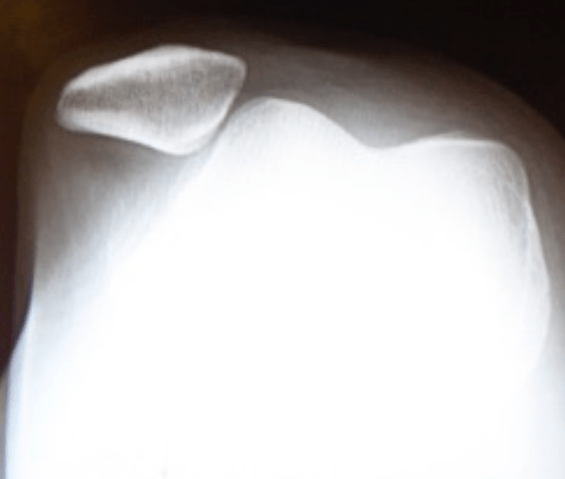

X-ray of a dislocated kneecap. Note the kneecap sitting outside the groove it belongs in.